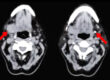

Η πιο κοινή ένδειξη για εγχείρηση στον παρωτιδικό αδένα είναι η παρουσία ενός όγκου στον αδένα. Οι περισσότεροι όγκοι των σιελογόνων αδένων είναι καλοήθεις και αναπτύσσονται στον παρωτιδικό αδένα. Το ανώδυνο πρήξιμο είναι το πιο κοινό σύμπτωμα. Οι διαδικασίες απεικόνισης όπως η αξονική και η μαγνητική τομογραφία είναι διαγνωστικές και ενημερωτικές. Για κακοήθεις όγκους, η θεραπεία έγκειται στην εκτομή και την ακτινοβολία. Τα μακροπρόθεσμα αποτελέσματα εξαρτώνται από το στάδιο του όγκου. Οι παρωτιδικοί αδένες προσβάλλονται σε περίπου 85% των όγκων των σιελογόνων αδένων, ακολουθούμενες από τους υπογνάθιους και τους μικρότερους σιελογόνους αδένες, και περίπου το 1% εμφανίζονται στους υπογλώσσιους.

Η απεικόνιση πρέπει να γίνει πριν από μια επέμβαση. Κυρίως είναι μία ή περισσότερες εικόνες υπερήχων του όγκου που πρέπει να υποβληθούν σε χειρουργική επέμβαση. Σε ορισμένες περιπτώσεις, μια τομογραφία (MRI, CT) είναι χρήσιμη για τον προγραμματισμό της χειρουργικής επέμβασης.